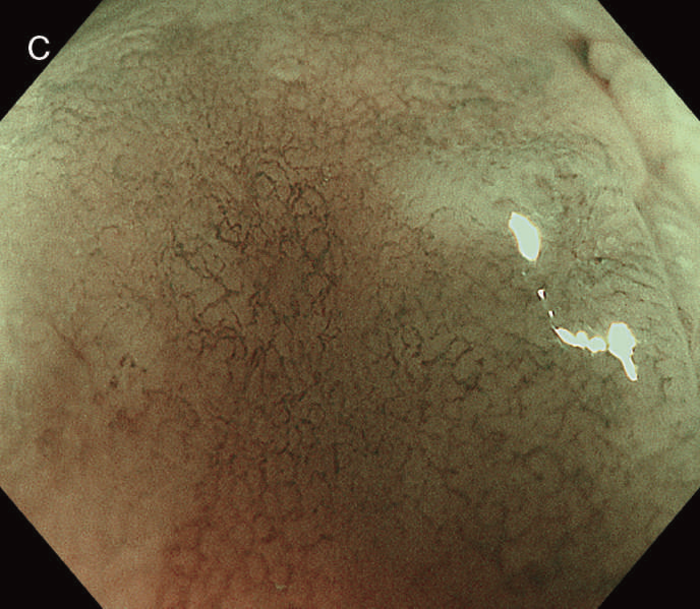

図12 Non-polypoid lesionの内視鏡所見

- 白色光観察

- インジゴカルミン散布像:境界がより明瞭に認識できる。

- 酢酸インジゴカルミン混合液(AIM)散布像:病変全体と周辺粘膜とのコントラストが明瞭となる。

- NBI非拡大観察像:非拡大においても境界の認識は比較的容易となる。

- NIBI拡大観察像:病変中心部では拡張した血管を認める。

- クリスタルバイオレット染色拡大観察像:病変中央では大腸不動の拡張したpitを認める。gの病変辺縁ではpit構造の違いにより周辺粘膜と病変の境界が認識できる。